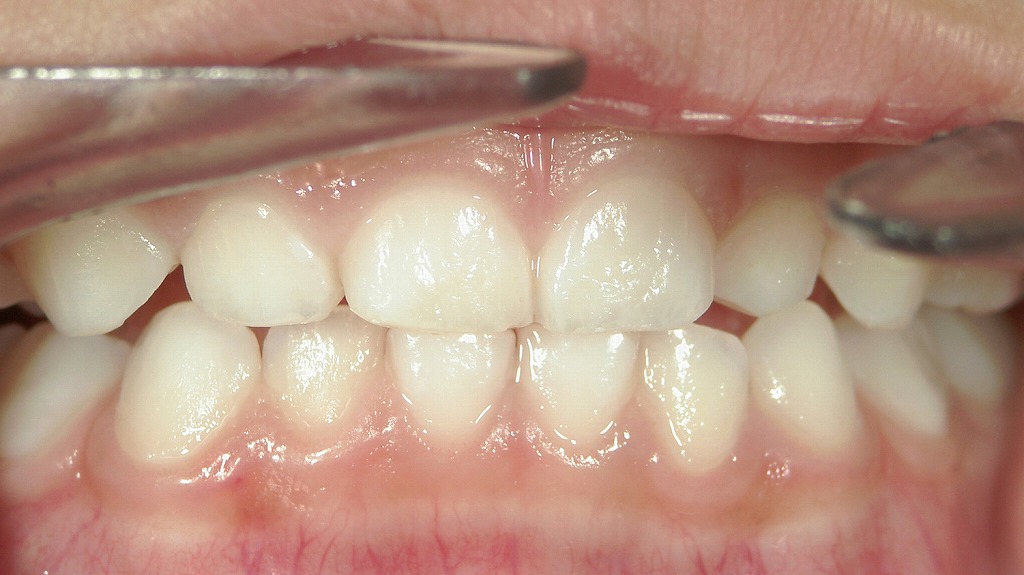

📷霊長空隙が存在する症例

乳歯の歯と歯の間にほとんど隙間がなく、全体的にキュッと詰まっている状態が確認できます。

本来、乳歯の時期は永久歯が大きくなるスペースを確保するために、**歯と歯の間に自然なすき間(霊長空隙・発育空隙)があるのが理想です。

この症例のように隙間がない場合、永久歯が生えてくる際に歯並びがガタつきやすい(叢生になりやすい)**傾向があります。